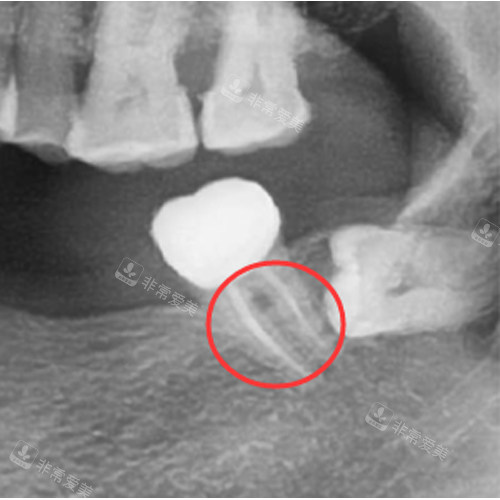

诊疗区域严格按照卫生标准进行设计和布局,每个治疗室都配备了可靠的口腔诊疗设备,如智能化口腔全景机、种植机等。

这些设备不仅能够提高诊断的比较准性和治疗的结果,还能减少患者的痛苦和治疗时间。